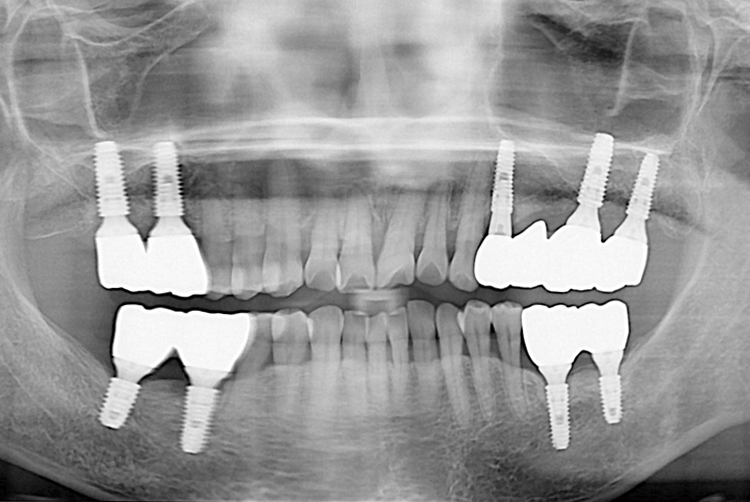

치료후 : 2018-08-10

세종치과는 많은 환자와 다양한 케이스를 바탕으로 항상 편안한 임플란트 수술을 제공하고자 노력하고,

오래동안 튼튼히 쓸 수 있는 임플란트 수술을 가장 큰 목표로 삼고 있습니다